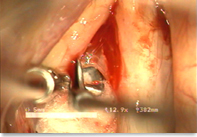

Dr. Kim, the director of Yeson Voice Center released his new research findings in the book under the title of ‘Diagnostic characteristics of ruptured cyst and the usefulness of Advancement Mucosal Flap of Vocal Folds (Co-writers Hyun Soo, Kim, Hee Ro, Youn and Ji Wook, Lee)’ It’s hard to di…